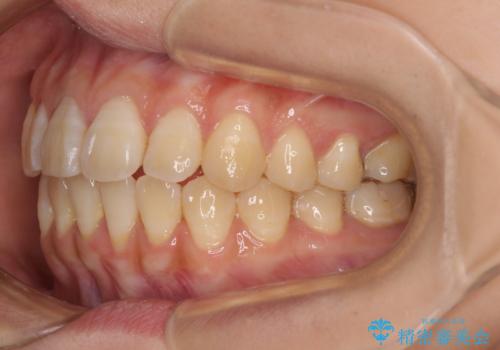

舌の突出癖による開咬と前歯の突出 インビザライン矯正治療

- 上下前歯の非接触と叢生を気にして来院された患者様です。

開咬の改善はインビザラインの最も得意とするところであるため、インビザラインを用いて矯正治療を行うこととしました。

治療開始直後に上顎前歯に激しい痛みが発現し、矯正治療を休んだり、マウスピースの装着時間を短くしたりと工夫をしましたが、残念ながら治療途中で失活していることが分かりました。

矯正治療の途中で前歯の根管治療とオールセラミッククラウンによる補綴治療を行い、その後インビザライン1セットを用いて細かい部分を仕上げました。